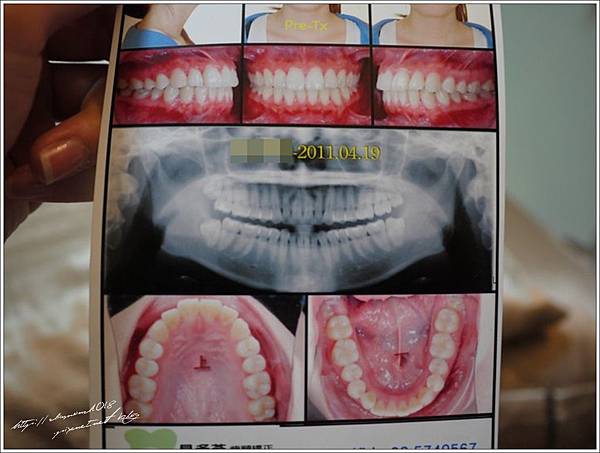

這上一篇應該有放過了

我是2011年4月去新竹的貝多芬牙醫諮詢

當天聽完解說就做了齒模(自費!費用可抵牙套費用)

先給大家看看我的牙齒兒吧

國中時期~高中時期

醫生看過後給我的建議有兩個

1. 拔上下排左右分別第四顆牙 2. 拔四顆智齒

最後我選擇了第一種方案(每個人情況不一樣要問醫生才準喔)

我選擇的矯正器是比較不痛的"戴蒙"